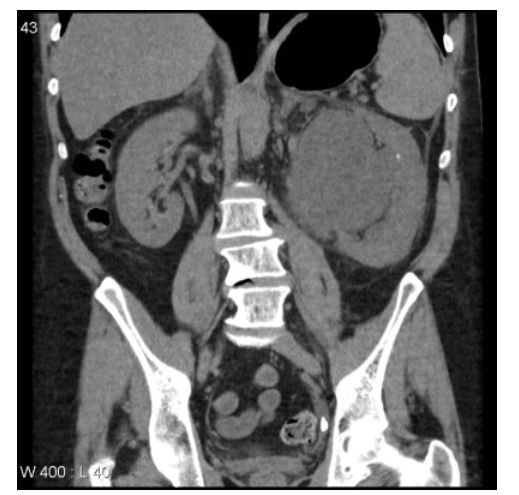

• massive hydronephrosis

• a small calculus in the left kidney.

• A single large calculus is present distally in the left ureter with accompanying hydroureter.